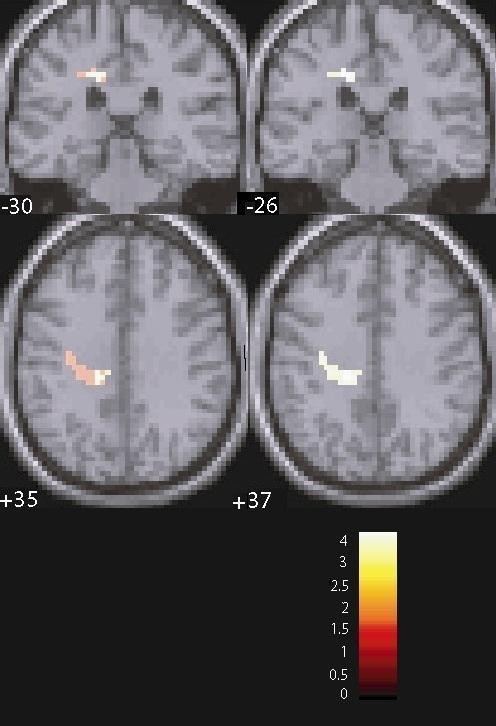

MDD patients exhibited smaller activation than healthy controls (HC) in the left middle cingulum (T = 3.82, P = 0.041, FWE corrected for multiple comparisons) and left insula (T = 4.19, P < 0.001, uncorrected), which also showed a trend for significance after correction for multiple comparisons (P = 0.072) (Figure 1). Smaller activation in the left insula was also found in the MDD group when compared to the FHN group (T = 4.43, P = 0.033, FWE corrected for multiple comparisons). Further, MDD patients had smaller activation in the left post-central gyrus when compared to FHN participants (T = 3.59, P < 0.001, uncorrected), although this difference did not survive FWE correction. Finally, the FHP group had greater activation in the right Heschl's gyrus when compared to the FHN group (T = 4.60, P = 0.018, FWE corrected for multiple comparisons) (Figure 2).

Interestingly, when compared to the FHN group, the FHP group exhibited activation differences in the right Heschl's gyrus. In this area, FHP participants had greater activation for contrast F > N and smaller activation for contrast F < N. The Heschl's gyrus is a subregion of the superior temporal gyrus that, apart from being functionally involved in auditory processing, plays an important role in emotional processing, theory of mind and empathy [39, 40]. Volumetric reductions in this area have been found in MDD patients, even after recovery from the disease [41]. Moreover, similar results have also been shown in bipolar disorder patients [42]. Our results implicate activation differences in superior temporoparietal areas between individuals with and without family history of MDD during exposure to fearful facial expressions. As only the right hemisphere was involved, our findings might also suggest a lateralization effect. This is perhaps in line with previous fMRI research suggesting a role of the right Heschl's gyrus during exposure to emotional (auditory) stimuli [43] and showing that the activation of auditory processing regions specialized for language, like the Heschl's gyrus, can be detected during performance in tasks requiring visual perception of the human face [44]. This might support the belief that this cortical area plays a role in acquired dynamic audiovisual integration mechanisms in the left superior temporal sulcus [44]. In this context, our results suggest a non-task specific role of the Heschl's gyrus in facial emotion processing, which is perhaps lost in MDD.